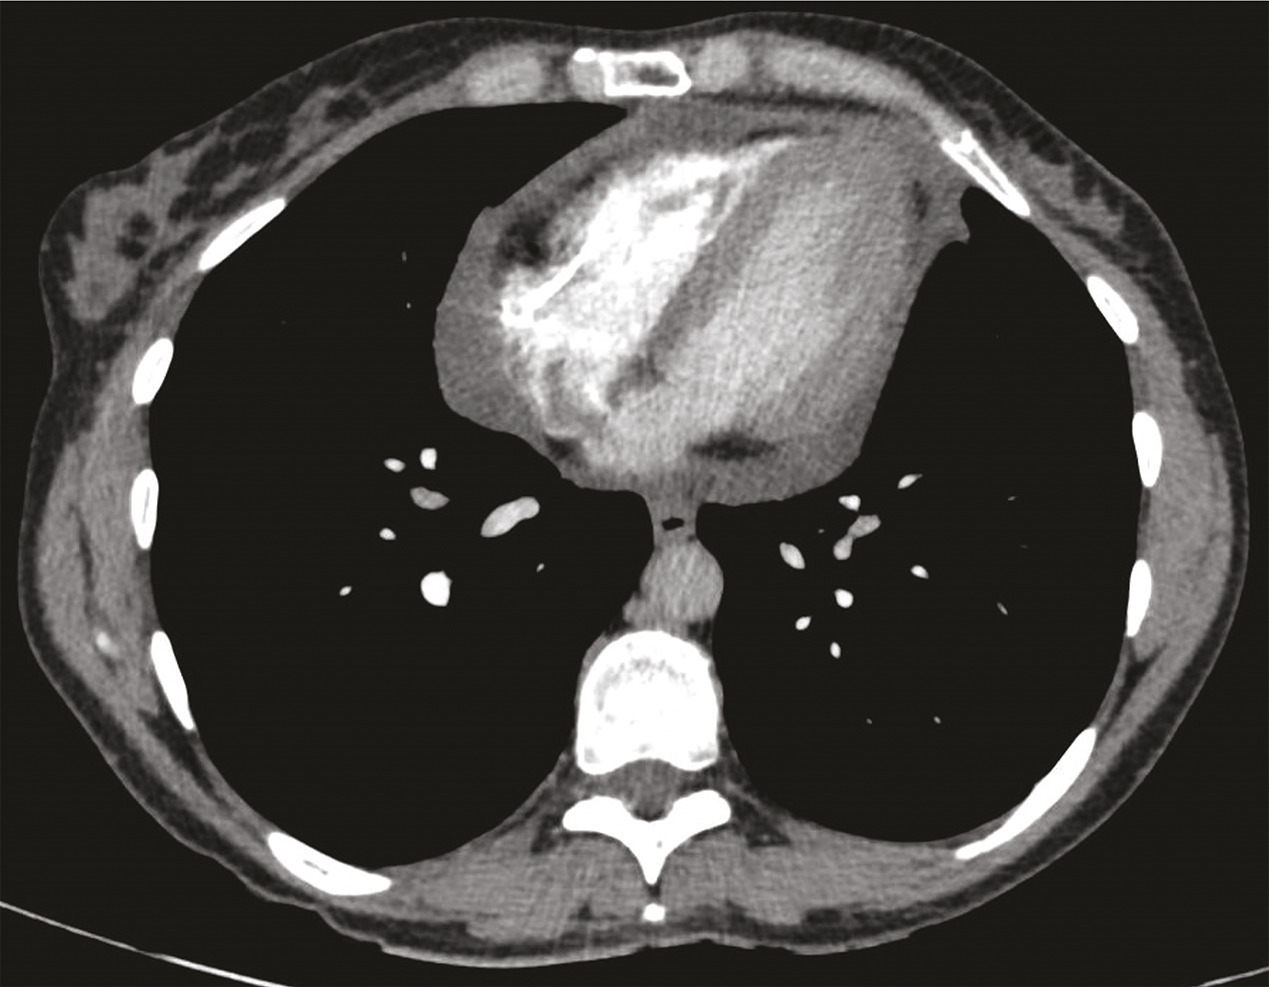

La radiographie de thorax est le plus souvent normale lorsque l’épanchement est modéré. La tomodensitométrie thoracique (fig. 1) peut être utile pour confirmer le diagnostic et rechercher une cause sous-jacente telle que la tuberculose ou un cancer.

L’imagerie par résonance magnétique (IRM) cardiaque (fig. 2) confirme l’inflammation du péricarde, ce dernier étant épaissi et brillant en T2 et rehaussé après injection de gadolinium, et permet de rechercher une myocardite associée. Les biopsies péricardiques sont réservées aux tamponnades récidivantes, aux suspicions de péricardite bactérienne ou néoplasique, et aux cas de péricardites s’aggravant sous traitement sans cause définie.

Le diagnostic est conforté par la tomodensitométrie et l’IRM cardiaque, qui permettent la mesure de l’épaisseur du péricarde (> 4 à 6 mm), la recherche de calcifications et de signaux inflammatoires. L’échocardiographie montre une fonction systolique conservée, des anomalies de la fonction diastolique et des anomalies de la cinétique du septum interventriculaire. Le Doppler du flux transmitral montre un profil restrictif. Un cathétérisme cardiaque est parfois nécessaire pour confirmer le diagnostic, notamment en cas de difficultés échographiques.